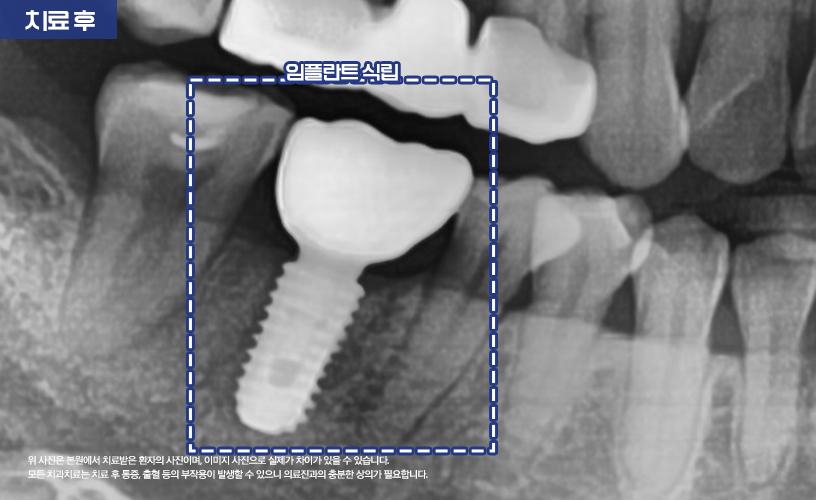

이후 뼈이식을 통해 뼈가 추가적으로 녹는 걸 예방하고

임플란트 식립이 이루어져 치료가

마무리되었습니다.

"치아 파절 치료 사례"

상기 환자분은 치아 파절로 인해

본 원에 내원하시어 치료한 사례입니다.

환자분의 경우 어금니 부분에 크랙이 있으신 상태로

지내시다가 균열이 점점 커지고 치아 뿌리까지

염증이 심해져 치아가 파절되었습니다.

보다 자세한 상태를 확인하기 위해

정밀한 검진이 이루어졌습니다.

환자분의 경우 치근단병소로 인해

치조골이 소실되어 있는 상태였습니다.

이런 경우 발치 및 염증 제거 치료가

먼저 진행되었습니다.